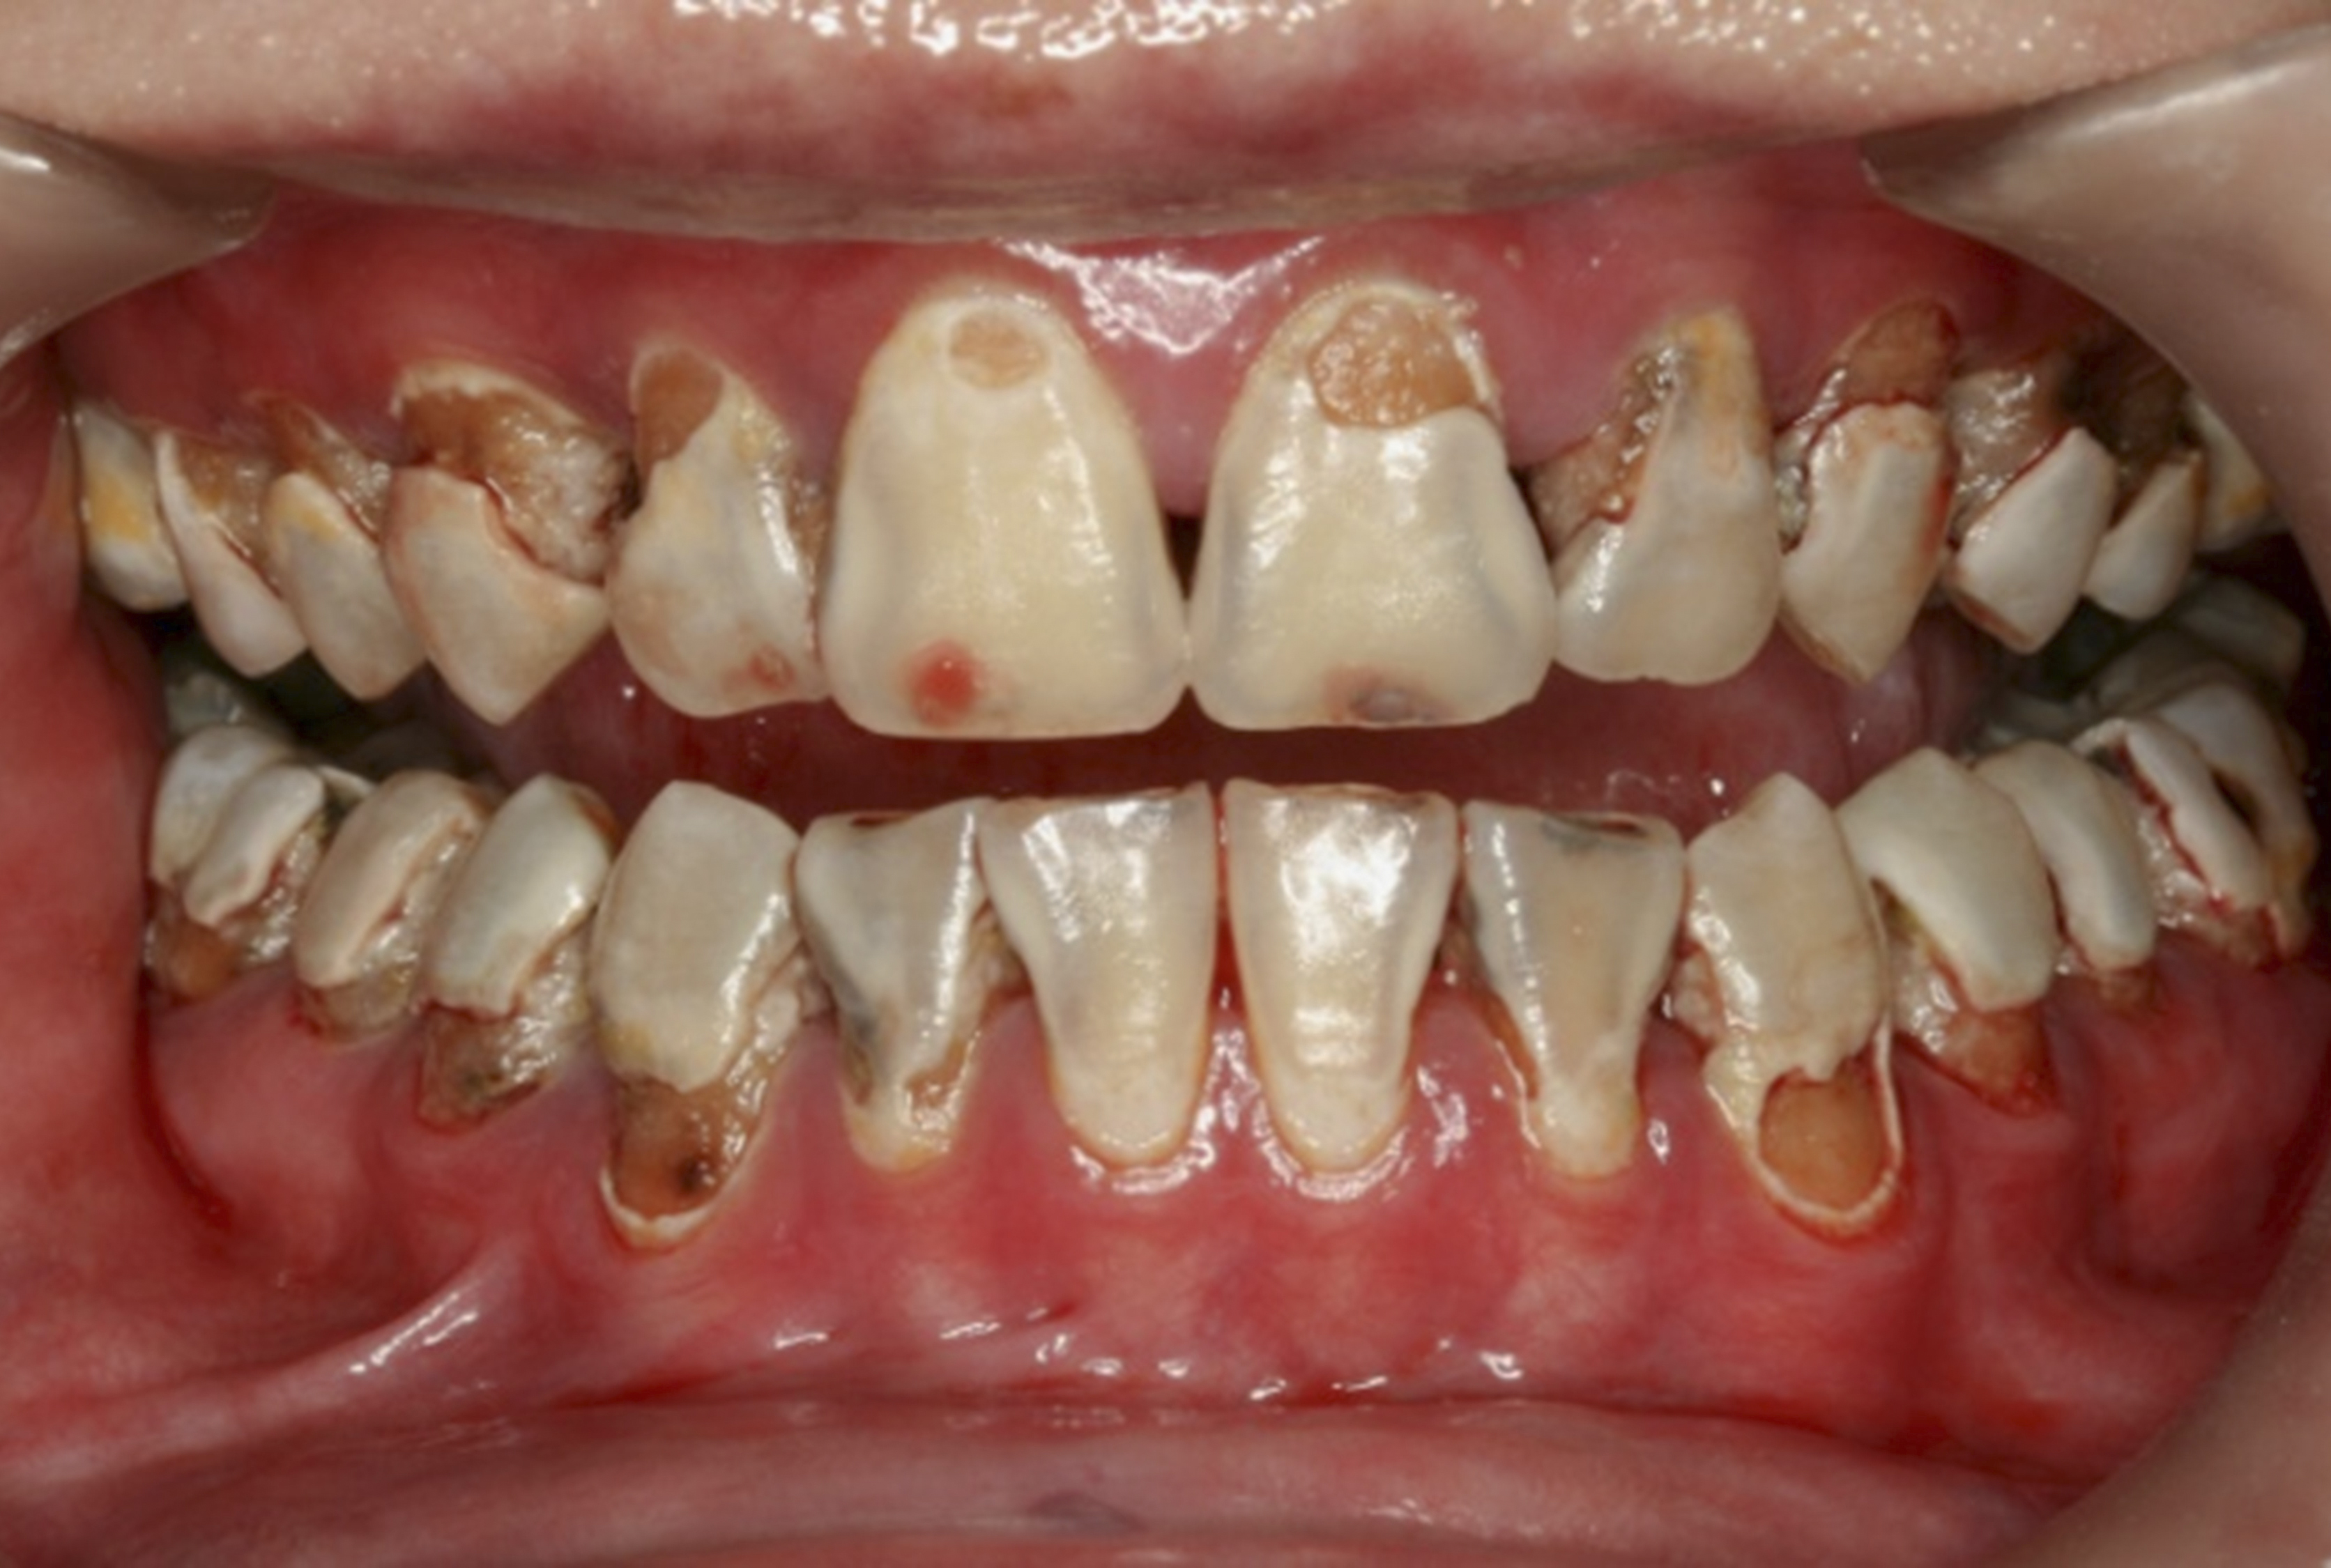

There are several advantages of using SDF in dental treatment. First, it showed an antimicrobial activity against mono-species, dual-species, and multi-species cariogenic biofilm.14-16 Silver ions are bactericidal metal cations that inhibit biofilm formation.17 Studies have indicated that silver interacts with sulfhydryl groups of proteins and DNA, thus altering hydrogen bonding and inhibiting respiratory processes, DNA unwinding, cell-wall synthesis, and cell division.18 At the macro level, these interactions affect bacterial killing and inhibit biofilm formation.17 Second, fluoride promotes caries lesion remineralization. Fluoride has been indicated to react with hydroxyapatite and generate calcium fluoride, which is a reservoir of fluoride, and facilitate further remineralization.19 An ex vivo study reported surface microhardness of the surface layer of the arrested caries after SDF applications was comparable with the unaffected sound dentin20 (Figure 1 and Figure 2). This is consistent with another study, in which a high remineralized zone was observed on the surface of arrested caries from exfoliated teeth with SDF treatment21 (Figure 3 and Figure 4). Third, its application procedures are simple and do not require injection or drilling, and the treatment does not involve expensive support infrastructure equipment such as piped water and electricity. The simplicity of the treatment is conducive to treating caries in apprehensive young children who may have intense dental fear, uncooperative patients with special needs, or elderly patients who have difficulty adapting to traditional dental care. It also allows trained workers to deliver the treatment to people who live in the area but who may not be able to easily access dental service.22 Patient compliance and satisfaction is often good when the patient is provided a clear explanation of the treatment outcome.23,24 Finally, the cost of SDF treatment is low and should be affordable in most communities.

The inherent disadvantage of SDF is that the caries lesions will be stained black after SDF application. SDF stops caries progression by forming a hard, blackened, impermeable layer on the tooth surface that is resistant to caries (Figure 5 through Figure 9). The authors’ clinical observations are that the darker the color, the more likely the caries arrested. Some patients may not be pleased with the esthetics of this treatment outcome; therefore, it is important to inform the patients and parents (for child patients) about this treatment outcome. Moreover, SDF can stain clothes and the skin of the body. Though it does not cause any pain or damage, an SDF stain on skin cannot be easily washed away. It takes around 7 days for it to disappear, and the stain on clothes is permanent.22

Fig 8. Use of 38% SDF to arrest rampant caries in a young teenager. Fig 8: Pre-treatment intraoral frontal view of rampant caries. Fig 9: Frontal view of arrested caries after consecutive application of SDF for 3 weeks. (images from Chu, et al, 201436 [reprinted with approval])

Figure 8

Fig 9. Use of 38% SDF to arrest rampant caries in a young teenager. Fig 8: Pre-treatment intraoral frontal view of rampant caries. Fig 9: Frontal view of arrested caries after consecutive application of SDF for 3 weeks. (images from Chu, et al, 201436 [reprinted with approval])

Figure 9